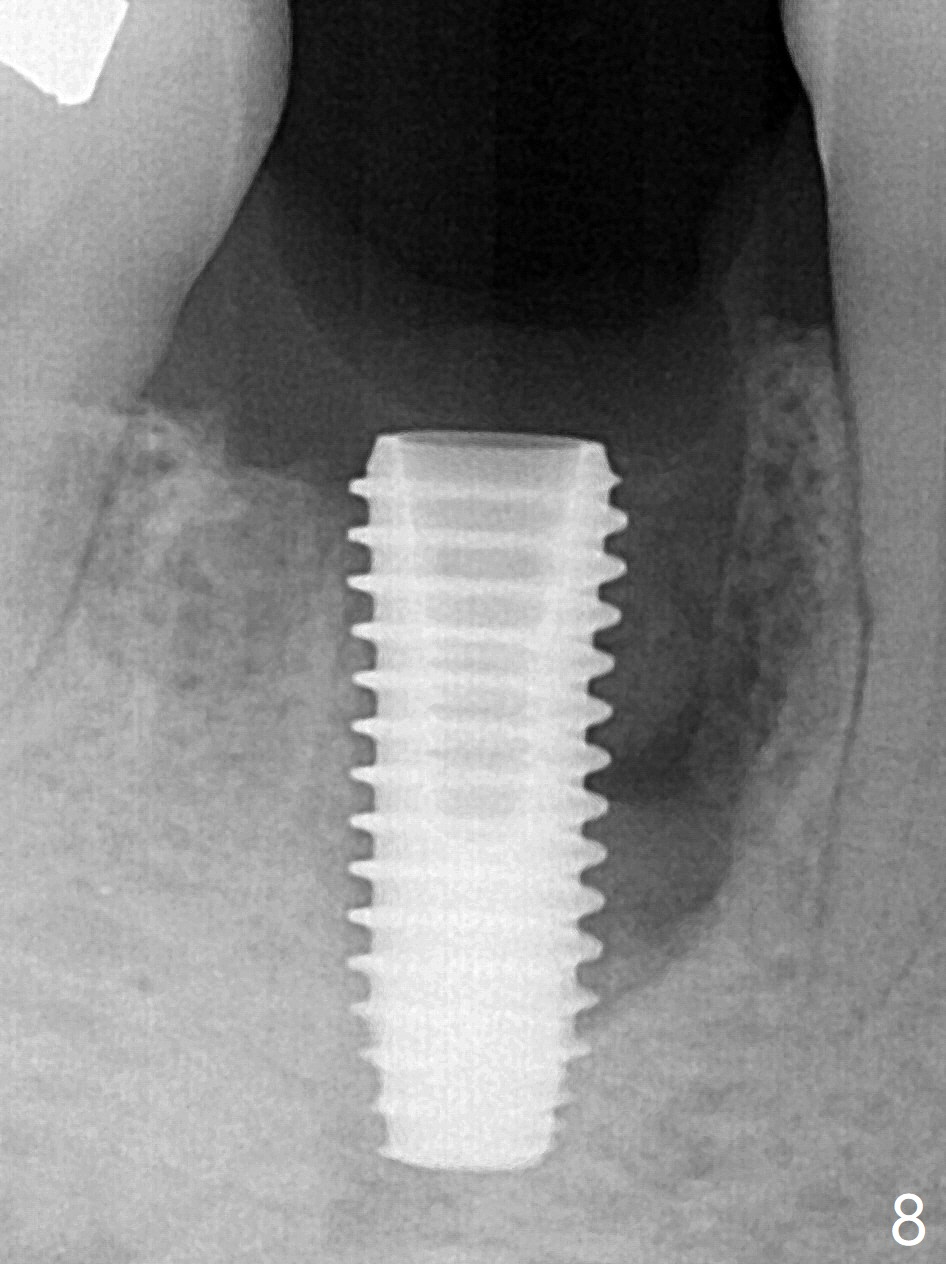

Preop oral Amoxicillin seems to be associated with reduction in the buccal and lingual (Fig.3 arrow) fistulae at #30, but there is mesiobuccal swelling (Fig.1 *) with 7 mm pocket (Fig.2). Osteotomy is initiated in the middle of the septum (Fig.3-5 S). As the osteotomy increases, it shifts mesially (Fig.6 arrow). Guided surgery is able to reduce shifting. A 5x13 mm implant is not seated completely (Fig.7) apparently due to osteotomy shifting. After removal of the bone from the osteotomy distally, the implant remains unseated with lower torque value (Fig.8). Following reuse of the 4.3 mm drill deeper by 1-2 mm, the implant is seated to a satisfactory depth (Fig.9 with increase in torque to 50 Ncm) with placement of Vera Graft (*) and a 7.5x4(3) mm abutment. After a second round of allograft placement (Fig.10 *), the implant is found to be 4 mm from the IAC. At the later stage of osteotomy, the coronal end of the septum is destroyed with loss of osteotomy depth landmark. It is apparent that the soft tissue landmark may be more reliable. The implant threads appear to be covered by the bone graft 3.5 months postop (Fig.11). The abutment is changed to 6.5x5(3) mm one before impression with minor margin prep. The bone density seems to increase 5 months postop, i.e., immediately post cementation (Fig.12) and 10 months postop (5 months post cementation (after retightening abutment), Fig.13 (*)). Periimplantitis develops mesiobuccally, consistent with bone loss 1 year 7 months post cementation (Fig.14 *); the implant seems to have been buccally placed. Bone graft is necessary with PRF or GEM21S if the vein is small and 6-month membrane with a hole around a 7.5x4(4) cemented abutment for easy wound closure. Take 5x5 CM CBCT to determine which wall has defect, buccal or lingual. Check mesial contact. If so, remove the crown, reseat the abutment (possible incomplete seating) and re-impress after bone graft.